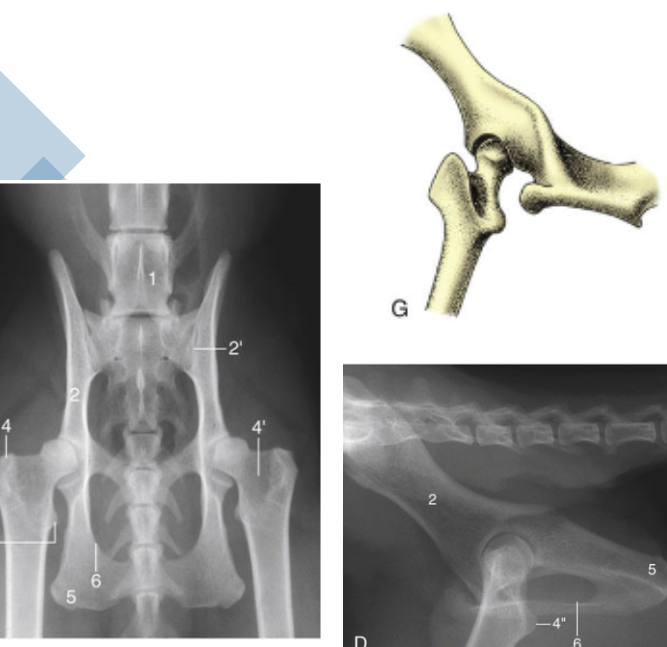

Coxofemoral

Pelvic Symphysis